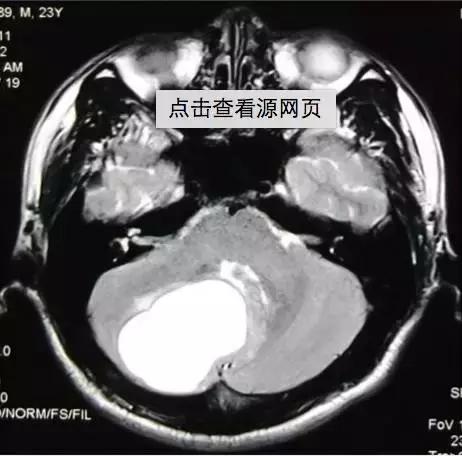

皮样囊肿破裂